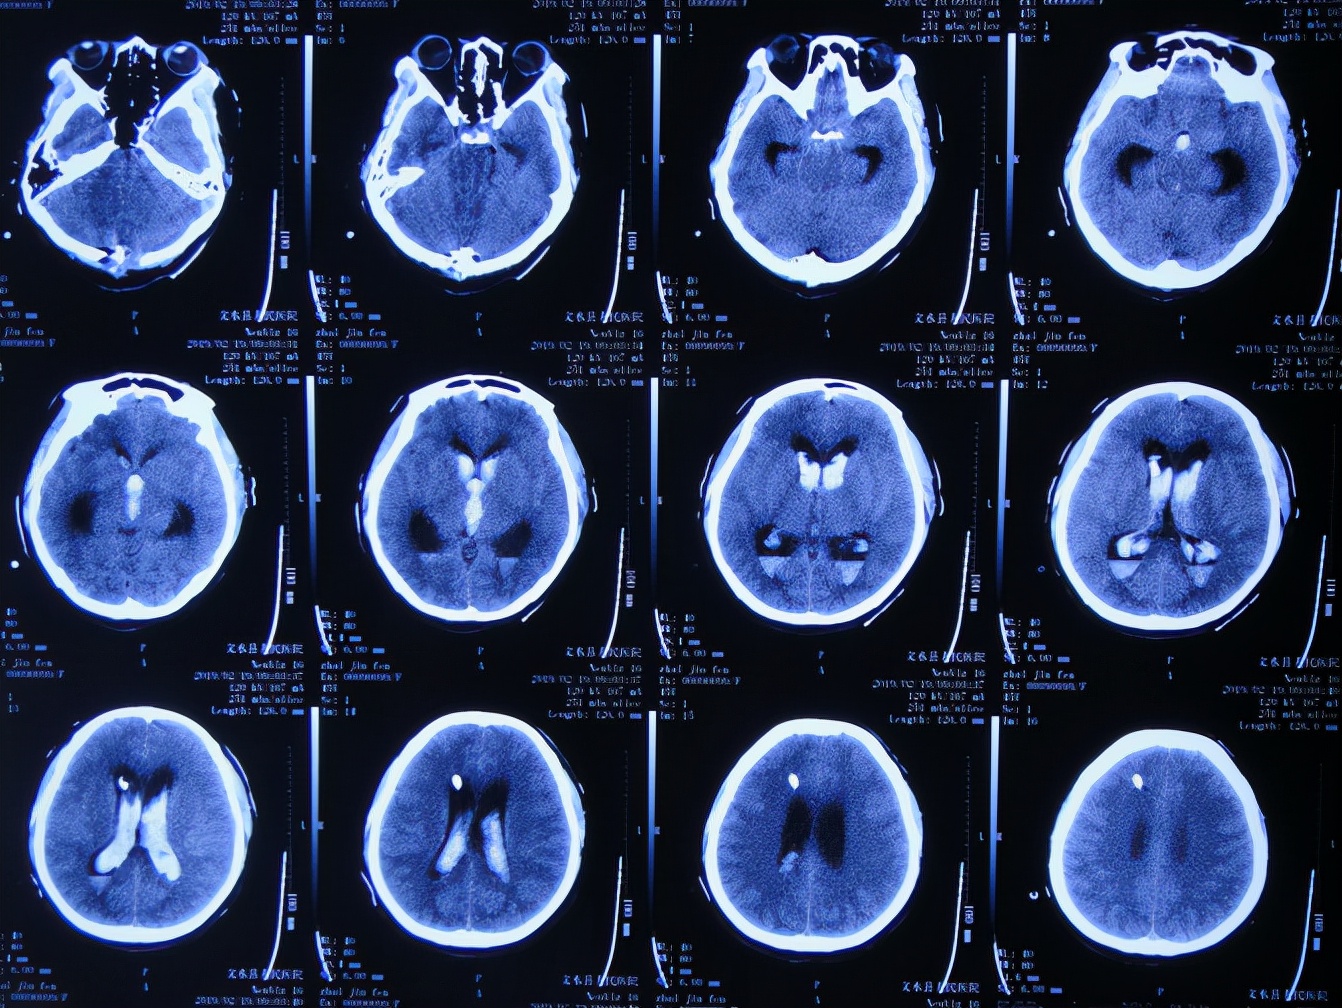

脑出血脑室外引流术后次日即2019年2月19日,复查头颅CT示出血未见明显减少( 图-3 )。

图-3: 2019年2月19日头颅CT